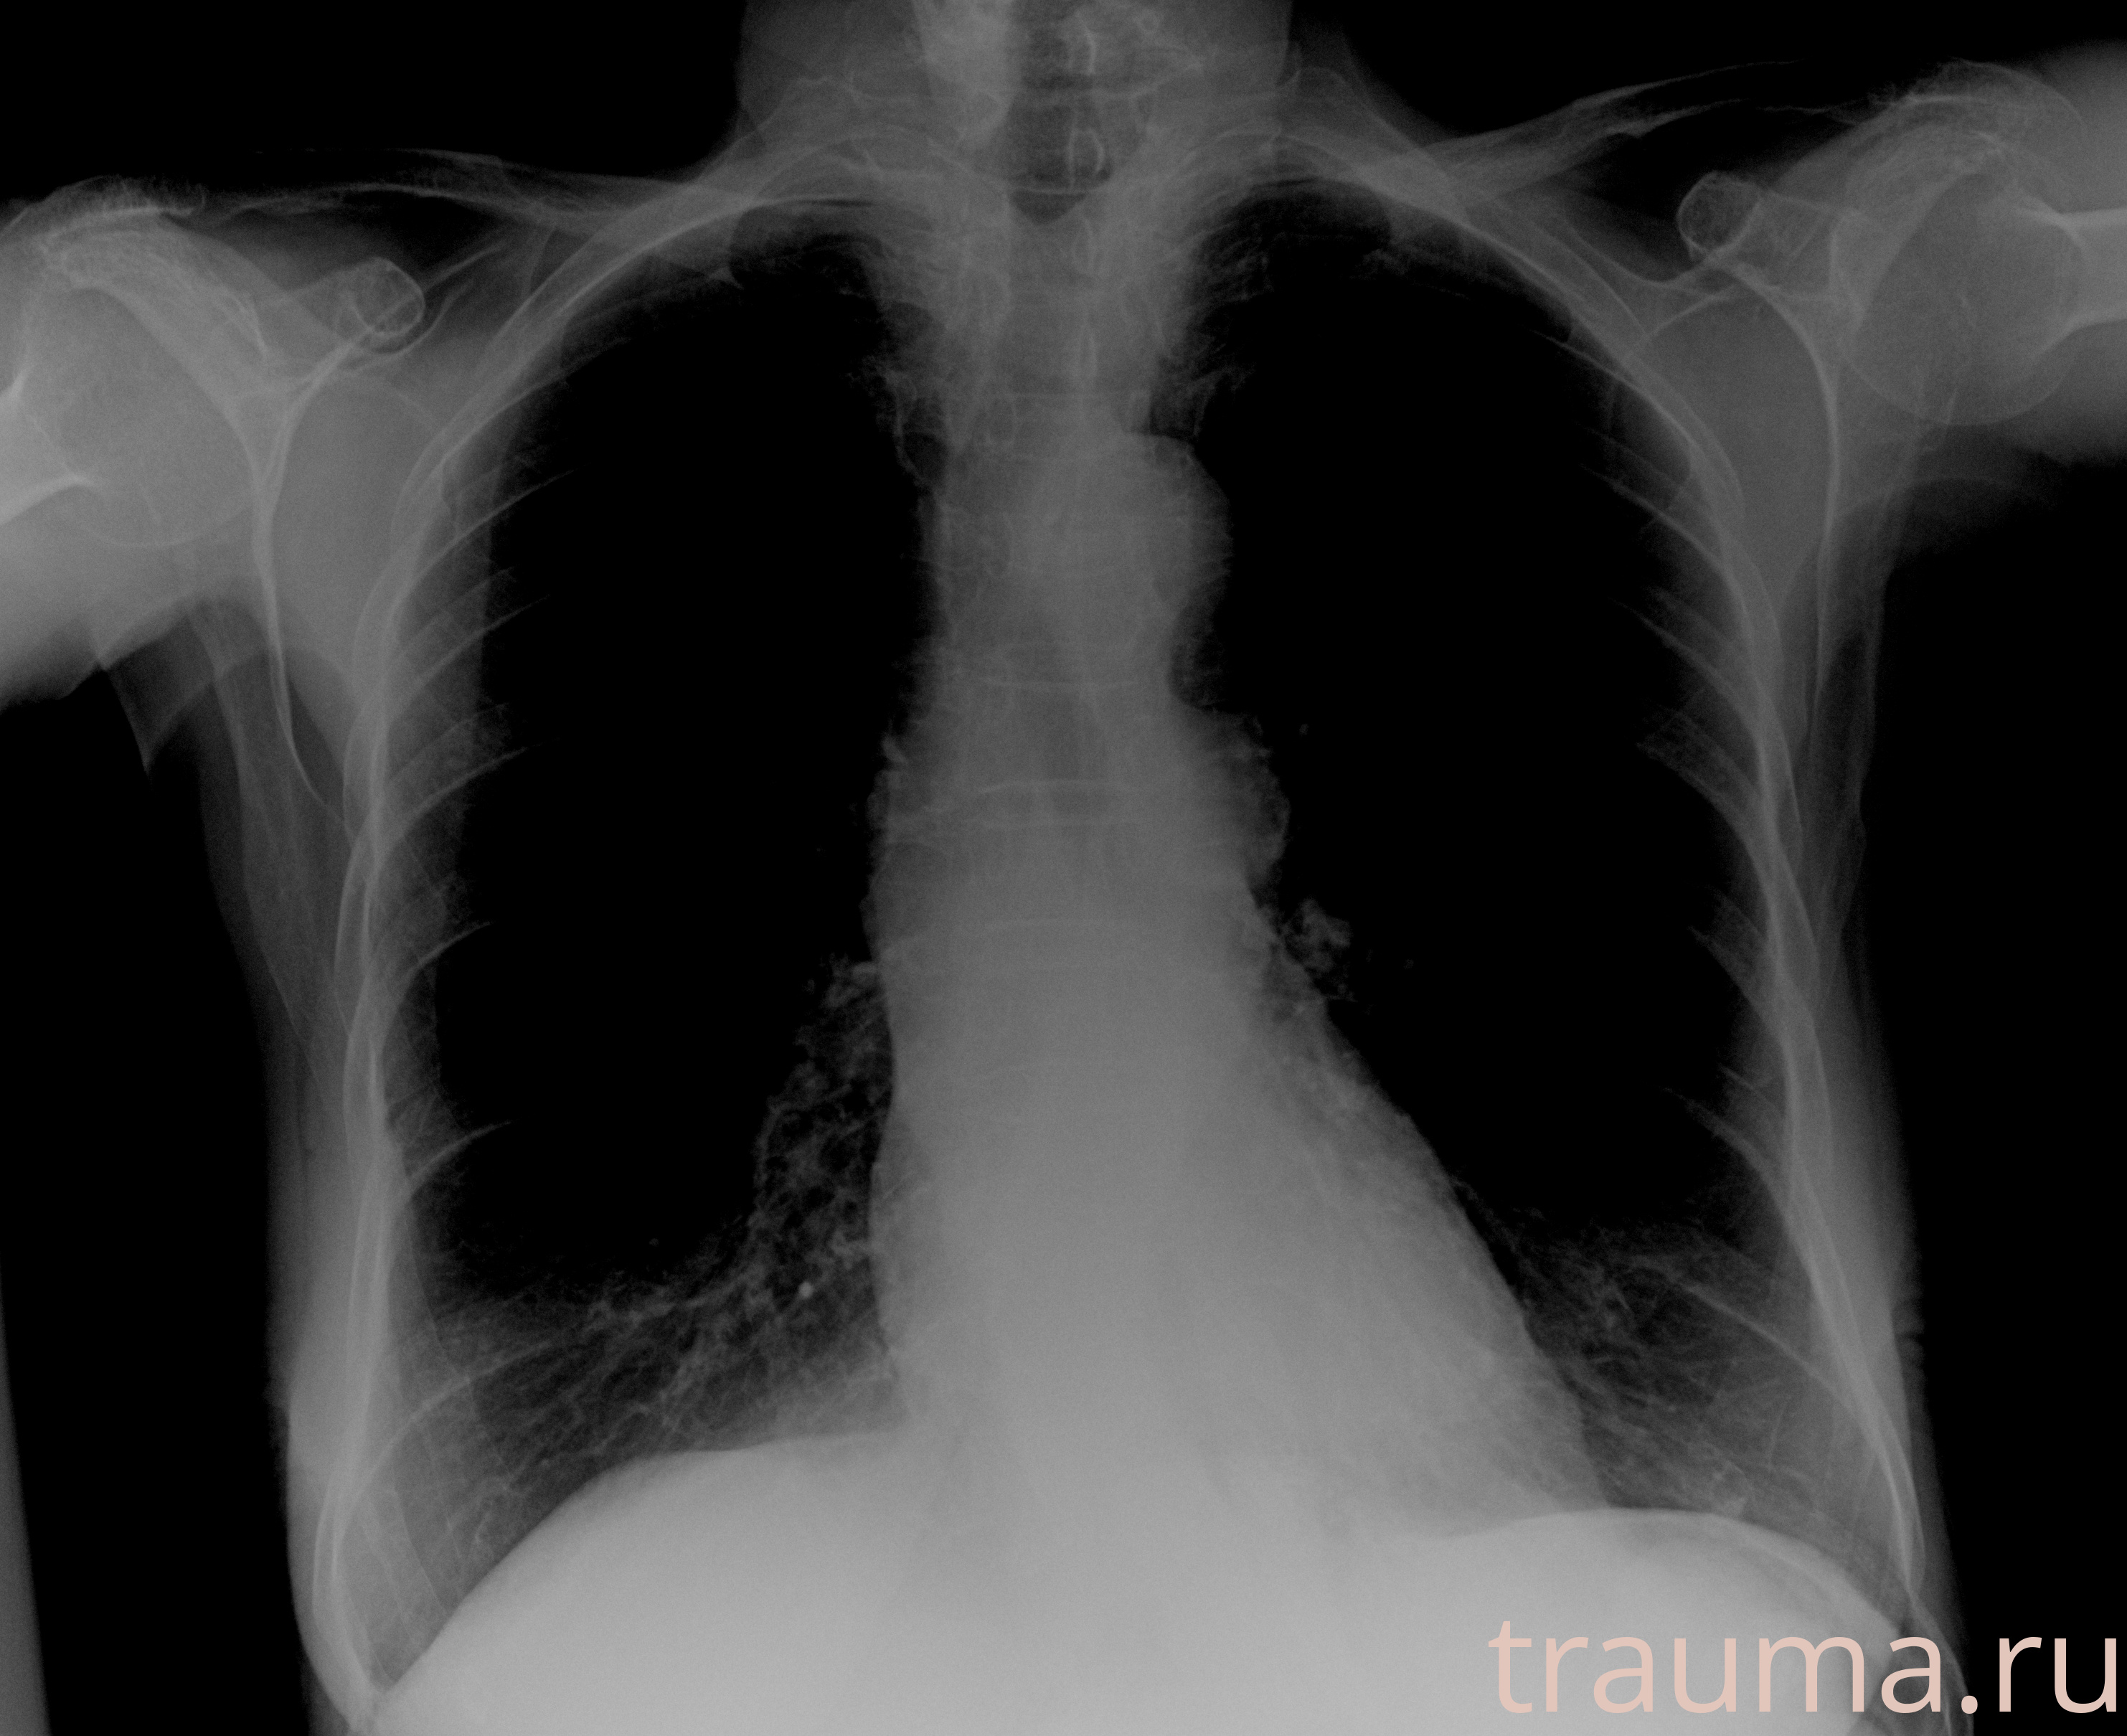

Рентгенограммы

Рентген на дому: по вашему адресу приезжает врач-рентгенолог, травматолог-ортопед с мобильным рентгеновским аппаратом, проводит диагностику травмы или заболевания, делает необходимые рентгенограммы, дает рекомендации по дальнейшему лечению. Получить качественные снимки в домашних условиях возможно благодаря уникальной методике, разработанной МосРентген Центром для института  Склифосовского

при переломе шейки бедра и пневмонии от компании МосРентген Центр - партнера Института имени Склифосовского